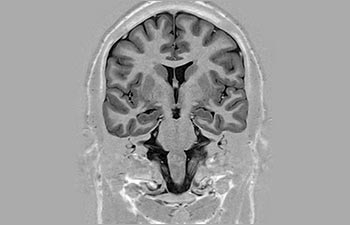

Sehen Sie selbst, was die ersten Nutzer von Ingenia Prodiva 1.5T über ihre Erfahrungen mit dem System und dessen Auswirkung auf ihre radiologische Praxis berichten.

Mehr Diagnosesicherheit in der Neuroonkologie